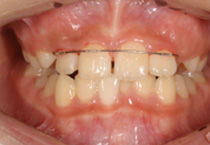

Case 2

Smile Line case 2 2022.08.28

2022.08.28

Smile Line case 2 2022.11.03

2022.11.03

Smile Line case 2 2022.11.24

2022.11.24